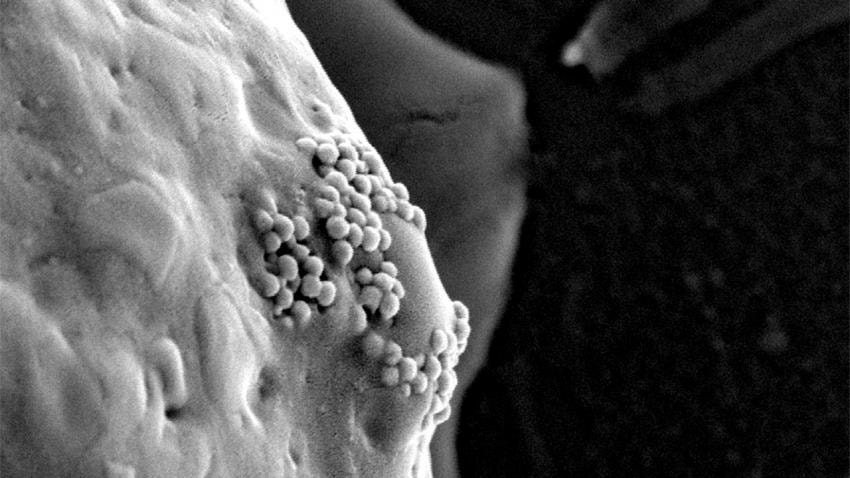

Os investigadores, após realizarem vários testes laboratoriais em ratos, aos quais foram inoculadas células cancerígenas, verificaram que ao injetarem nanoparticulas de ouro na corrente sanguínea, estas se alojam, na grande maioria nas células doentes.

Estes aglomerados de átomos de ouro podem assim detetar e ser indutoras para mais tarde matar as células cancerosas, geralmente ficam no corpo após a cirurgia de remoção do tumor maligno, de acordo com um estudo de uma nova técnica de nanotecnologia.Os investigadores revelam que nos casos em que foi possível retirar cirurgicamente a maior parte do tecido canceroso, cem por cento dos animais, sujeitos ao tratamento de nanoparticulas de ouro e laser, sobreviveram, graças ao facto de que nenhuma célula doente residual permanecer viva.

A nova abordagem impediu na realidade que o calor se espalhasse para os tecidos normais circundantes, mas deu origem a um outro efeito ainda mais importante: as temperaturas, onde havia grandes aglomerados de nanopartículas de ouro, subiram de forma ainda mais elevada, vaporizando as moléculas de água adjacente.

Automáticamente os investigadores verificaram que no local aplicado pelo laser, surgiam pequenas bolhas de ar, que rapidamente expandiam e rebentavam, desfazendo em pedaços as células cancerosas.

Segundo Lapotko, "aglomerados de nanopartículas produzem nanobolhas, nas células cancerosas e não no tecido normal."